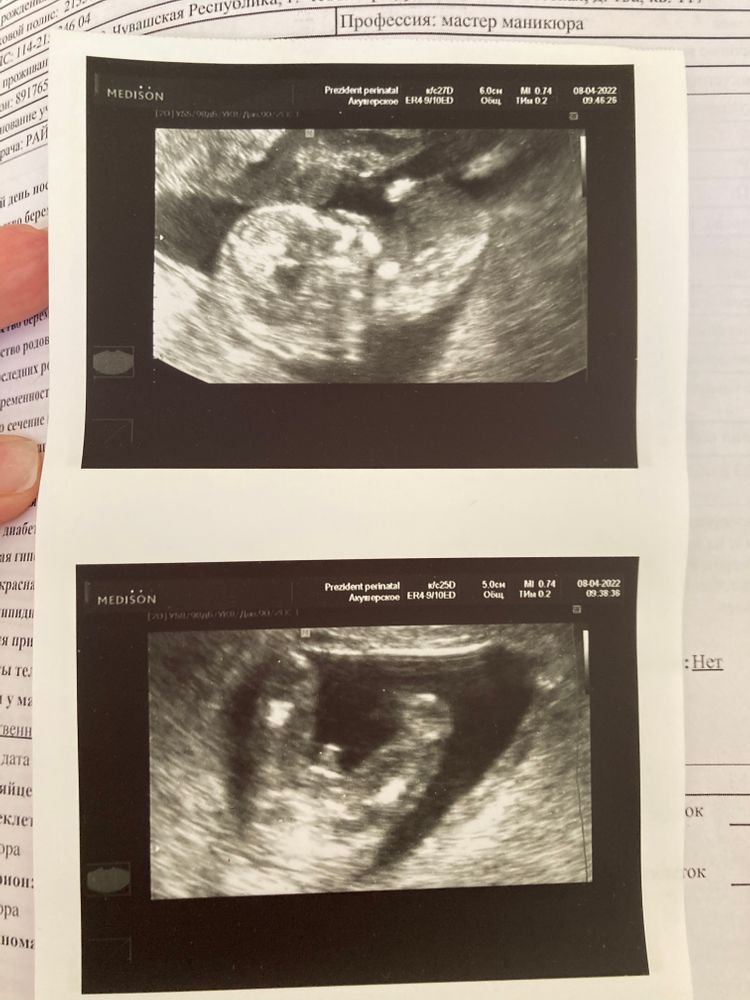

Я тут в 10 недель ходила сдавать анализ на пол - пришла девочка…

Если бы я знала какой хороший узист мне попадётся - я б не тратила в пустую 5000😹

Сделали сегодня скрининг УЗИ + кровь, по первому УЗИ сегодня 12+1, а по скринингу теперь 12+4 - т.е пдр 20 октября и эТо замечательно 😀

А, да, посмотрите фотки - 100% же девочка 🤣 нафига я делала анализ крови и так все видно😂 прямо откровенно не мальчик